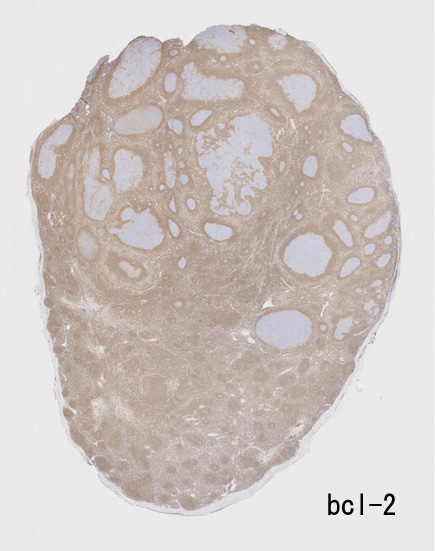

不整形の胚中心(CD20+, CD10+, BCL2-)のまわりにはCD5陽性リンパ球が多く存在してマントル層を形成している. (IgD染色でもマントル層はよく認識できる). 胚中心内のCD5+ cellはfollicular helper T-cellのようです.